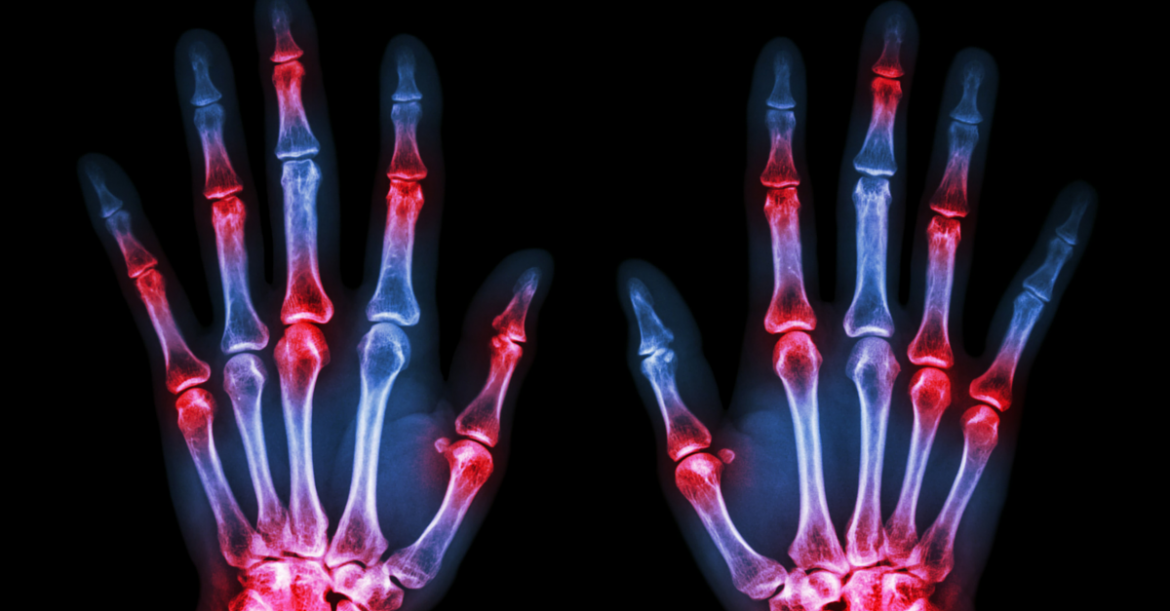

While arthritis typically affects joints — the word “arthritis” literally means joint inflammation: arth (joint) and itis (inflammation) – JA can involve the eyes, skin and gastrointestinal tract as well.

Whatever the causes, it is a chronic and painful disease. Having developed rheumatoid arthritis, I cannot imagine any child having to experience the pain associated with this disease or suffer the side effects of the current treatment options available.